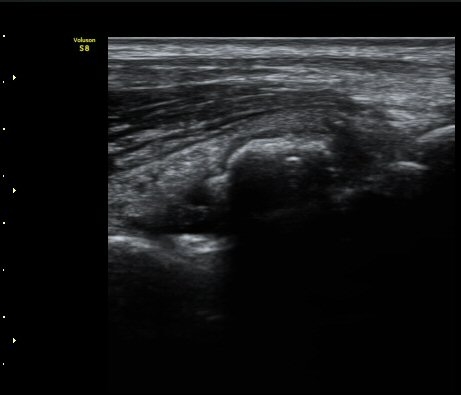

[ÆÈ²ÞÄ¡] ÆÈ²ÞÄ¡ °üÀý³» À¯¸®Ã¼¿¡ ÀÇÇÑ ÆÈ²ÞÄ¡ ÅðÇ༺ °üÀý¿°

¼ºº° / ³ªÀÌ

³²ÀÚ/ 44¼¼

ÁÖÁõ»ó

ÆÈ±ÀÄ¡ ÅëÁõ

ÃÊÀ½ÆÄ °Ë»ç